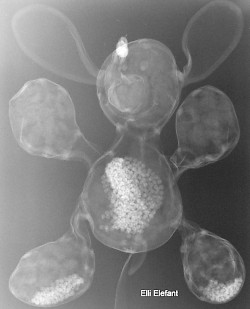

Erst das Kuscheltier - dann das Kind

Kinder kommen oft sehr ängstlich mit Kuscheltieren oder Puppen zum Röntgen. Um den Kindern diese Angst zu nehmen, kann man vor deren neugierigen Augen, zuerst die kuscheligen Begleiter unter die Röhre legen.

Spätestens wenn die Kinder die Bilder Ihrer Kuscheltiere sehen ist die Angst vorm Röntgen meist vergessen. So wie bei den unten abgebildeten Bildern.